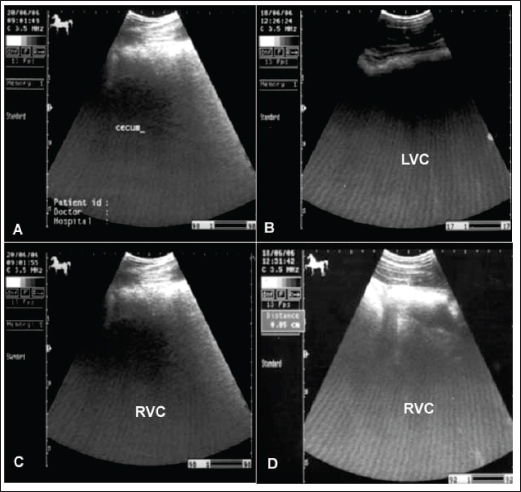

The cecum of horses with flatulent colic appears thin-walled due to gas distension; absence of sacculations; hypomotility on real-time ultrasonography, and the gases in the cecum prevent visualization of the ingesta inside the cecum (Le Jeune and Whitcomb, 2014). In comparison to healthy horses, the cecum is identified by its sacculations and contractions. The left ventral colon appears with a thin echogenic wall, the absence of sacculations, and the gases inside hinder the visualization of the ingesta. The right ventral colon compared to clinically normal horses shows the absence of sacculations and might be with thin or increased wall thickness, and this agrees well with Scharner et al., (2002), while in control horses it is characterized by the presence of sacculations, bright hyperechoic line, and the inability to identify the entire circumference of its wall (Fig. 5). Horses suffering from severe gas accumulation may collapse where postmortem examination confirms the diagnosis (Tharwat et al., 2008).

Fig. 6. Ultrasonogram of the cecum, left ventral colon (LVC), and right ventral colon (RVC) in 4 horses with flatulent colic. In A, the cecal wall appears echogenic in the absence of sacculations. In B, the LVC shows an echogenic wall with no sacculations. In C, the RVC shows a thin wall that appears echogenic in the absence of sacculations. In D, RVC appears in the absence of sacculations and with increased wall thickness. These organs contain a large amount of gas, which hinders their visualization.